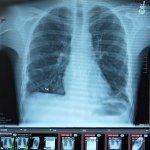

Only few imaging modalities lend themselves to imaging of the lungs. Conventional chest radiography is the most commonly used tool in the investigation of pulmonary pathology but yields the perhaps most difficult, plain radiographs to interpret.

Covid-19 causes characteristic changes in lung tissue visible in CT scans and chest radiographs, known as “ground-glass” opacities. Imaging is now considered a valid alternative, possibly even superior to RT-PCR. ‘This sparked an international debate about the role of CT in the diagnostic work-up of Covid-19,’ said radiologist Professor Cornelia Schäfer-Prokop.

A new X-ray technology has been used to identify a link between the damage that severe Covid-19 can inflict on lungs and pulmonary fibrosis, a disease that causes severe scarring of lung tissue.